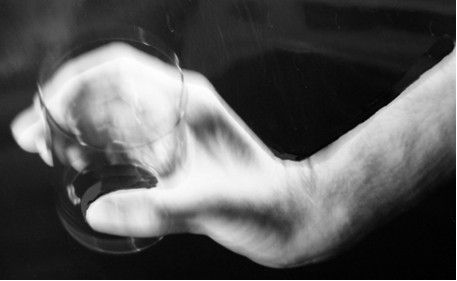

Prezentowana fotografia pokazuje możliwość chwytną ręką osoby po urazie rdzenia kręgowego i jest typowa dla porażonego z poziomu: